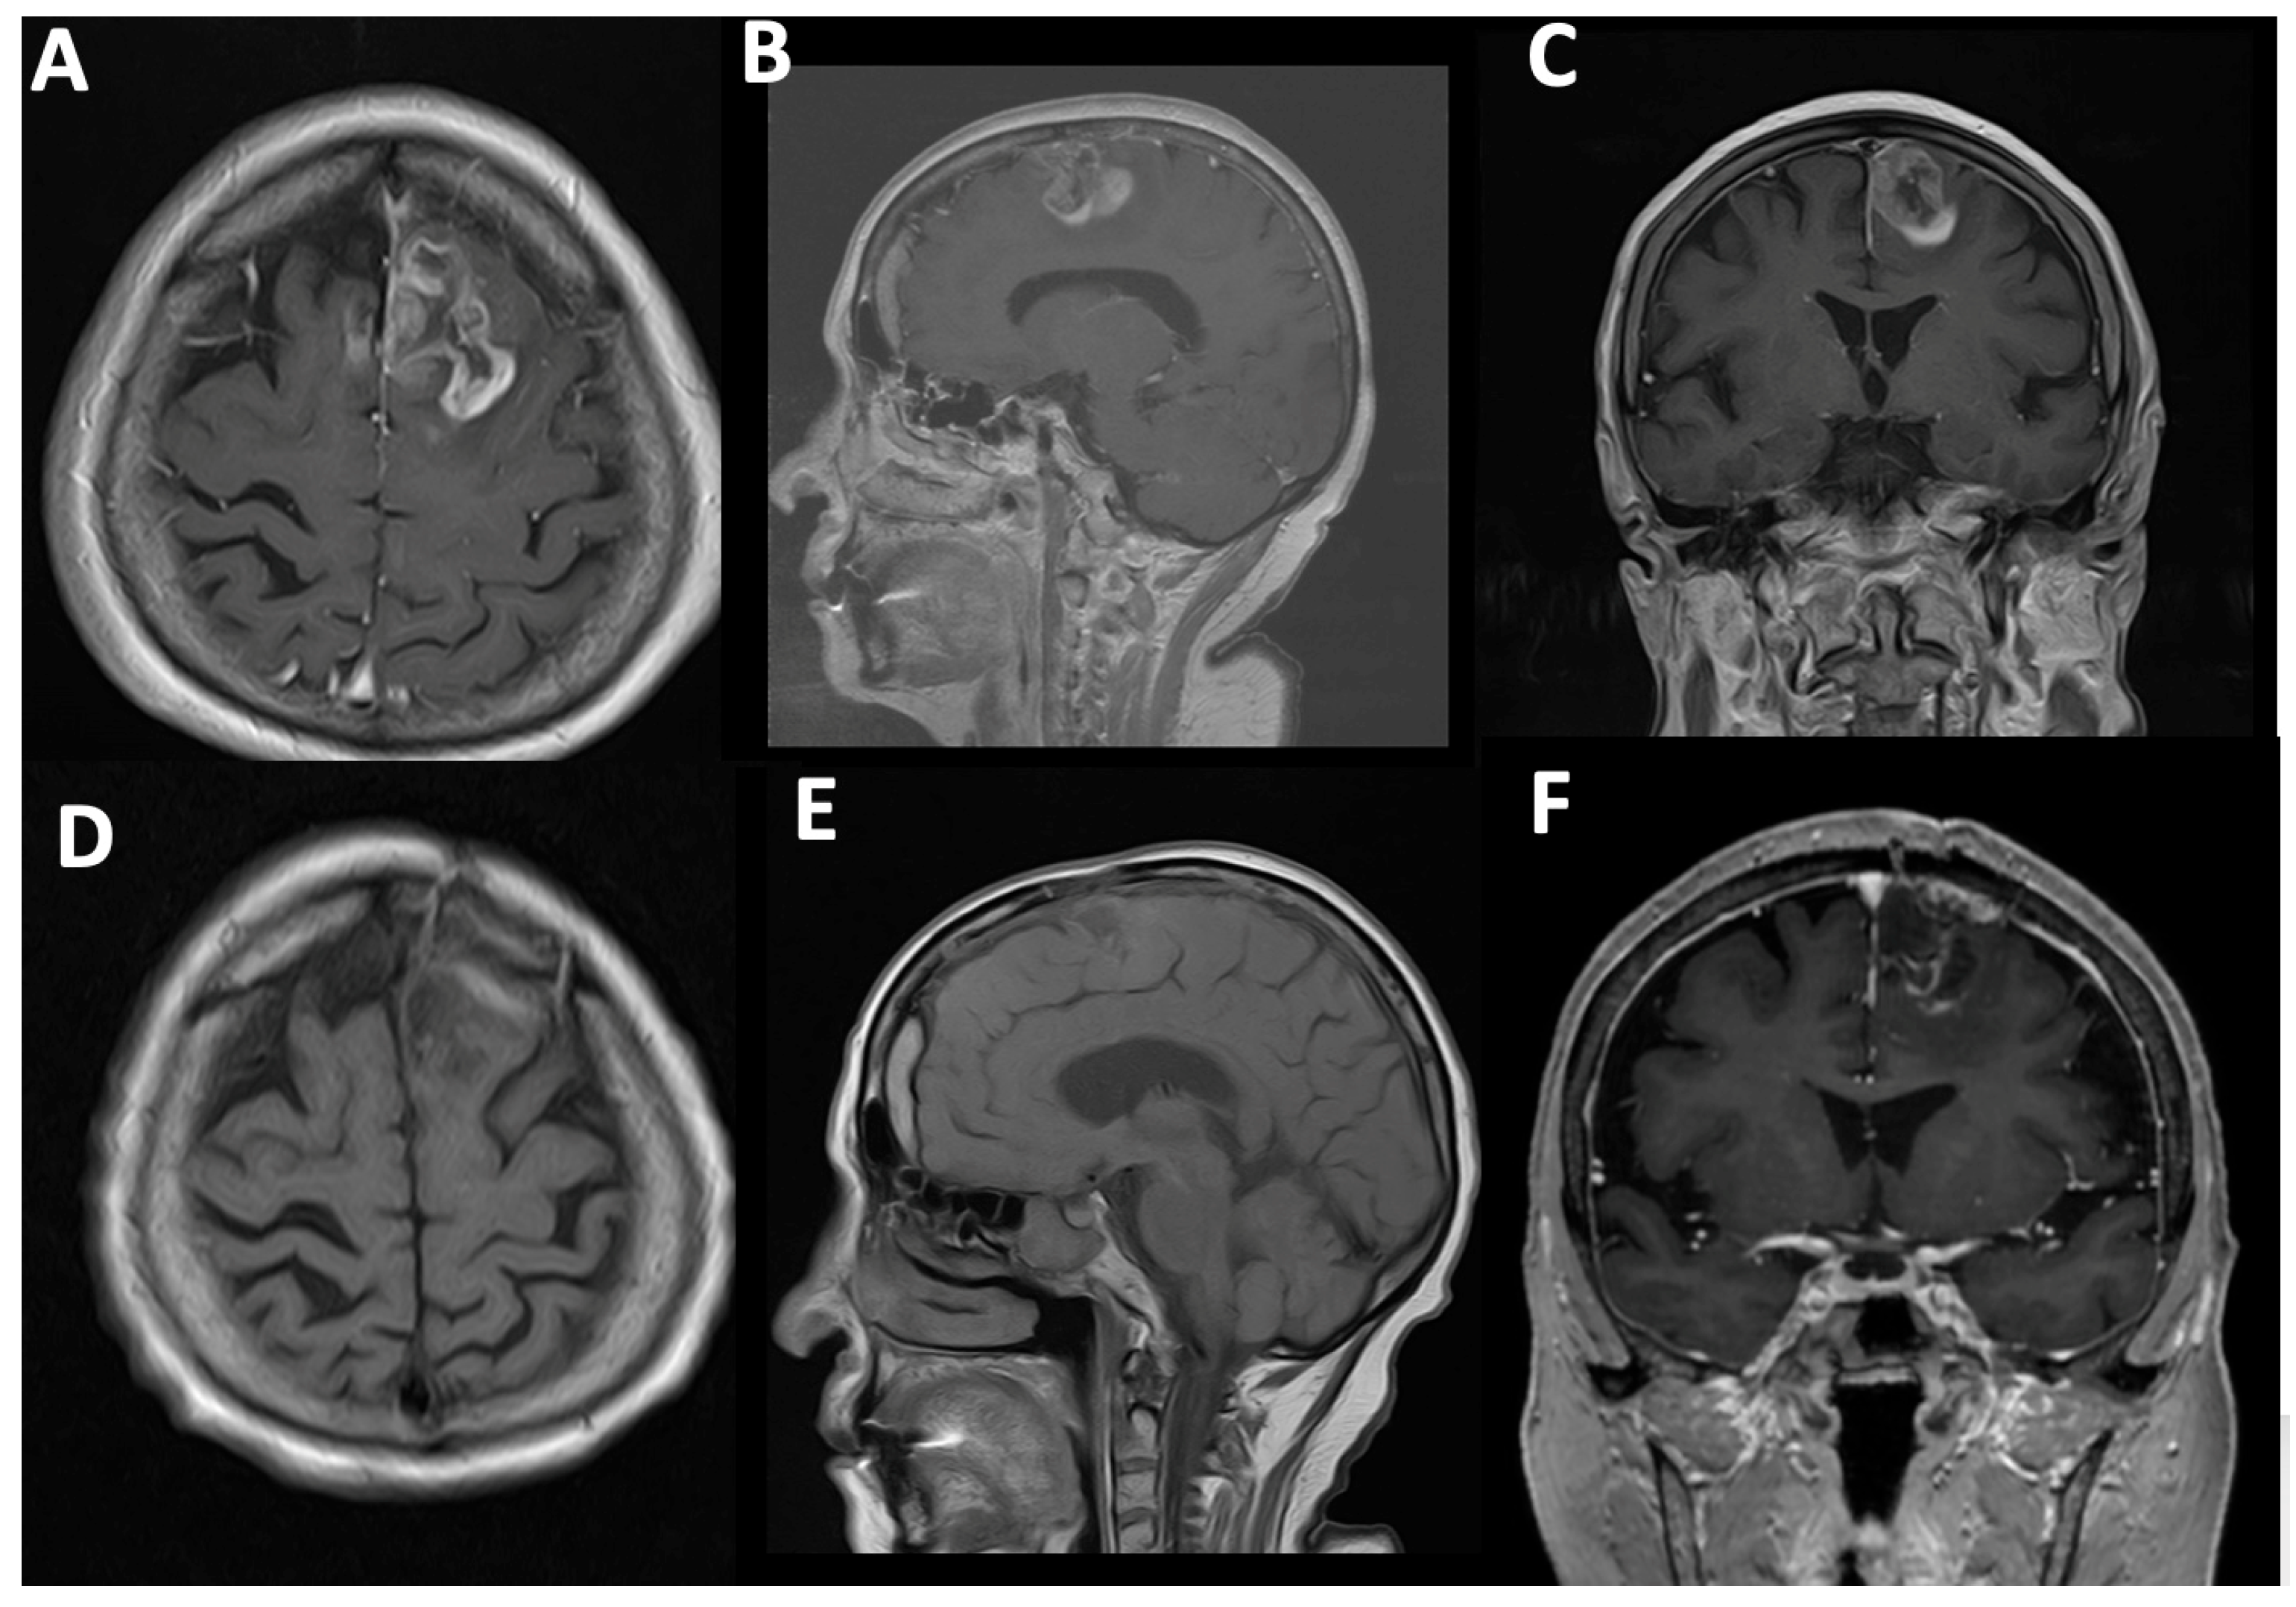

Case#1. A 73-year-old female with a medical history of arterial hypertension and diabetes mellitus presented with progressive headaches, dizziness, and cognitive decline. Family members also reported noticeable memory impairment. Neurological examination revealed motor aphasia and right-sided hemiparesis with a muscle strength of 4/5. The patient was alert with a Glasgow Coma Scale (GCS) score of 15 and had a Karnofsky Performance Status (KPS) of 70%. Preoperative contrast-enhanced MRI demonstrated a contrast-enhancing mass in the left frontal lobe with midline shift and mass effect, consistent with a high-grade glioma (Figure 4A–C). A chronic subdural hematoma was also noted in the ipsilateral hemisphere. The patient underwent successful resection via 5-ALA fluorescence-guided surgery. Intraoperative visualization under blue 400 nm light enabled maximal tumor delineation. Postoperative MRI confirmed complete removal of the contrast-enhancing component, with no residual visible tumor (Figure 4D–F).

Figure 4. Fluorescent guided surgery. (A) A 54-year-old female first presented with a stroke suspicion, but after a detailed investigation, a left frontal HGG with relevant mass effect was revealed. Before the operation, the relatives also noticed signs of memory loss. Neurological examination revealed right-sided hemiparesis. (AC) Preoperative T1-weighted contrast-enhancing images showing left frontal HGG. (DF) Postoperative T1-weighted contrast-enhancing images showing no contrast enhancement. (B,E) Note the chronic subdural hematoma.